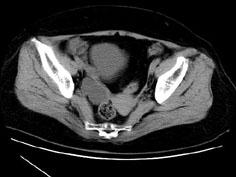

问题 女性,27岁,体检时B超发现右侧附件区囊性占位性病变,行CT检查,下列说法错误的是 ( )

选项 A、此为卵巢浆液性囊腺瘤 B、此为卵巢囊肿 C、病灶边界清晰 D、病灶为单房,壁薄,无分隔 E、病灶来源于右侧卵巢

答案 A